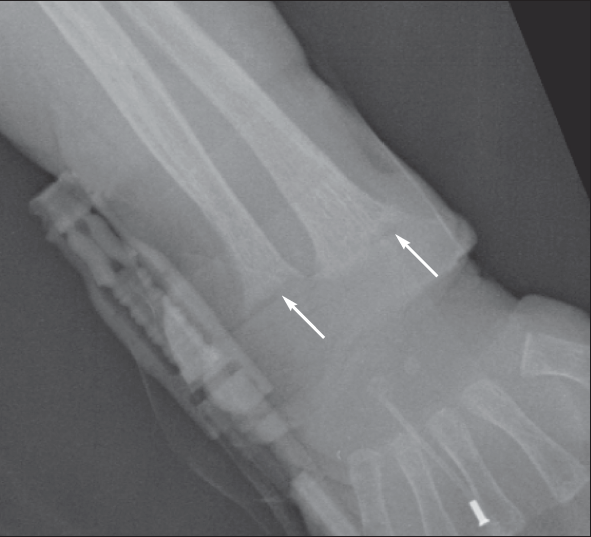

From www.consultant360.com

Vitamin D Deficiency Rickets Consultant360 Vitamin D Def Learn about the symptoms, causes and prevention of. There may be no symptoms and doctors don’t routinely check vitamin d levels, so many people are deficient and don’t realize it. The causes of vitamin d. This topic will review the definition, clinical manifestations, and treatment of vitamin d deficiency in adults. Vitamin d helps keep bones, teeth and muscles healthy. Vitamin D Def.